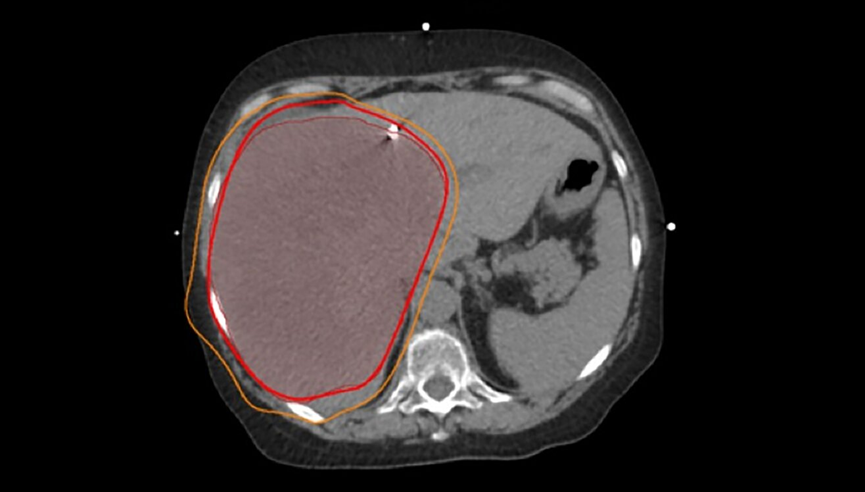

肝内胆管癌(发生在肝脏内部胆管的癌症)中,有一类肿瘤特别棘手,它们体积非常大,甚至超过10厘米。

一方面,要想对这么大的肿瘤产生效果,就必须用很高剂量的放射线,但肝脏本身承受能力有限;另一方面,这些肿瘤往往贴着胃、肠道等重要器官,一旦误伤,后果会很严重。